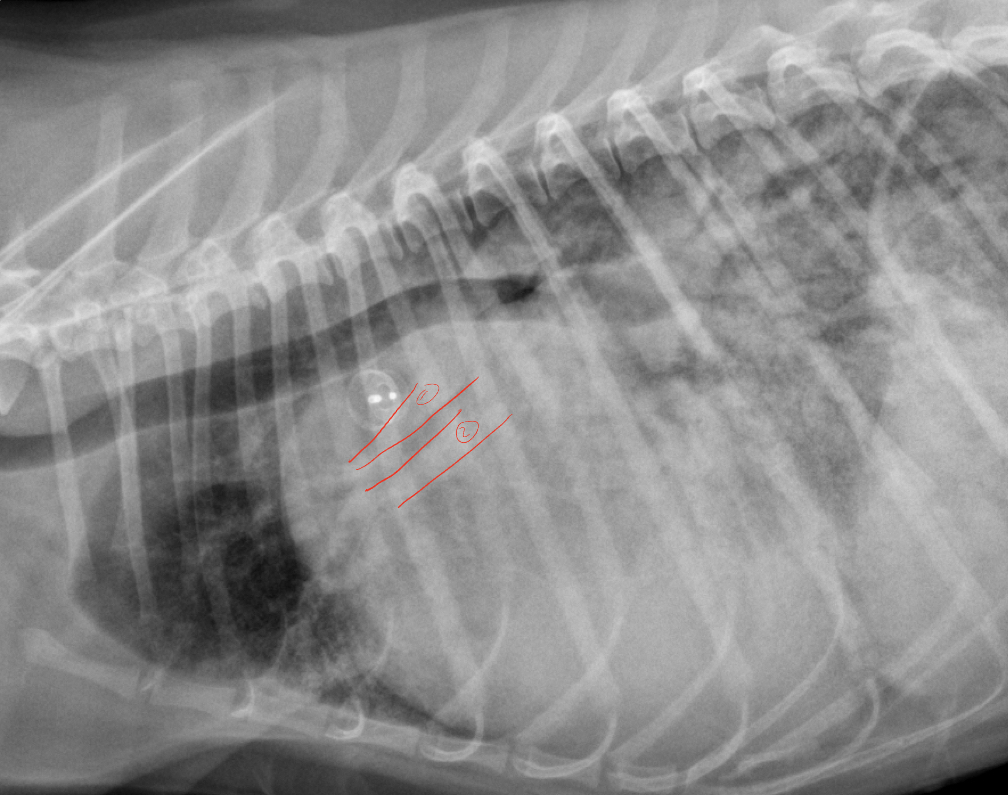

taken from 5yr old dog, identify 1+ 3, lung pattern and what is likely dx

A

1. Pulmonary artery (enlarged)

2. Pulmonary vein

Lung pattern: interstitial

Dx: heartworm disease